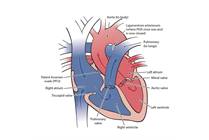

Hypoplastic Left Heart Syndrome

Hypoplastic left heart syndrome (HLHS) is a congenital heart defect where most of the structures on the left side of the heart are small and underdeveloped. The Hybrid approach, developed by surgeons at Nationwide Children's Hospital, is an alternative to Norwood open heart surgery for HLHS.

Atrioventricular Septal Defect (AVSD)

Atrioventricular septal defect (AVSD), also commonly known as endocardial cushion defect or atrioventricular canal defect (AVCD), is a heart condition where there are holes between the heart’s upper and lower chambers, and the valves controlling blood flow may not form correctly.

Double-Inlet Left Ventricle

Double-inlet left ventricle (DILV) is a heart defect where both upper chambers send blood to one lower chamber, causing mixed blood flow to the body and lungs. Most babies with DILV will need many heart surgeries over their lifetime. Most surgeries are successful, but your child will need cardiology care for life.

Bicuspid Aortic Valve

Bicuspid aortic valve disease (BAV) is an irregularity in the heart where there are only two leaflets on a valve, instead of the normal three.

D-Transposition of the Great Vessels

D-Transposition of the great vessels (d-TGA) is a congenital heart defect where the aorta and pulmonary artery are switched from their normal positions. Shortly after birth, babies with d-TGA are blue because not enough oxygen is getting to the body.

Congestive Heart Failure

Congestive heart failure (CHF) happens when the heart does not pump enough blood to the body for normal function and activity. When the heart is not pumping normally, fluid can build up in the lungs.

Heart Failure

Heart failure means the heart’s ability to squeeze is weakened. As a result, the heart cannot pump enough oxygen and nutrients to meet the body’s needs.

Coarctation of the Aorta

Coarctation of the aorta is a heart defect that is present at birth (congenital) in which the aorta is narrowed and results in decreased blood flow to the lower body. The left ventricle (pumping chamber) of the heart must work harder in order to pump blood through the narrowed aorta.

Ebstein's Anomaly

Ebstein’s anomaly is a heart problem that some people are born with. It means the tricuspid valve, which helps control blood flow in the heart, doesn’t work right. Most babies with severe Ebstein’s need surgery at some point.

Total Anomalous Pulmonary Venous Return (TAPVR)

Total anomalous pulmonary venous return (TAPVR) is a condition where the blood vessels in the lungs, called the pulmonary veins, are not attached to the heart in the right place. Because of this, the body can’t get enough oxygen.

Interrupted Aortic Arch (IAA)

Interrupted aortic arch is a heart condition where the aorta doesn't form completely. This affects blood flow and will require open heart surgery to treat it.

Truncus Arteriosus

Truncus arteriosus is a rare heart defect where only one large blood vessel forms instead of two. It can be treated with surgery.

Patent Ductus Arteriosus (PDA)

The ductus arteriosus is a blood vessel that is formed during fetal growth to provide blood flow between two of the major arteries in the baby’s body while in the womb.

Atrial Septal Defect

Atrial septal defects (ASD) are a congenital heart defect characterized by a hole in the wall (septum) that divides the upper chambers (atria) of the heart.

Double Outlet Right Ventricle (DORV)

Double outlet right ventricle (DORV) is a congenital heart defect where the two great arteries are both attached to the right ventricle. In DORV, the normally separated oxygen-rich arterial blood and oxygen-poor venous blood is mixed prior to leaving the heart.

Tricuspid Atresia

Tricuspid atresia, also sometimes called hypoplastic right heart, is a heart defect where the valve between the heart’s right atrium and right ventricle doesn’t form. Most babies with tricuspid atresia will need many heart surgeries over their lifetime.

Ventricular Septal Defect (VSD)

A ventricular septal defect (VSD) is a hole in the heart. It changes blood flow, making the heart work harder. It can be treated with surgery or catheterization.